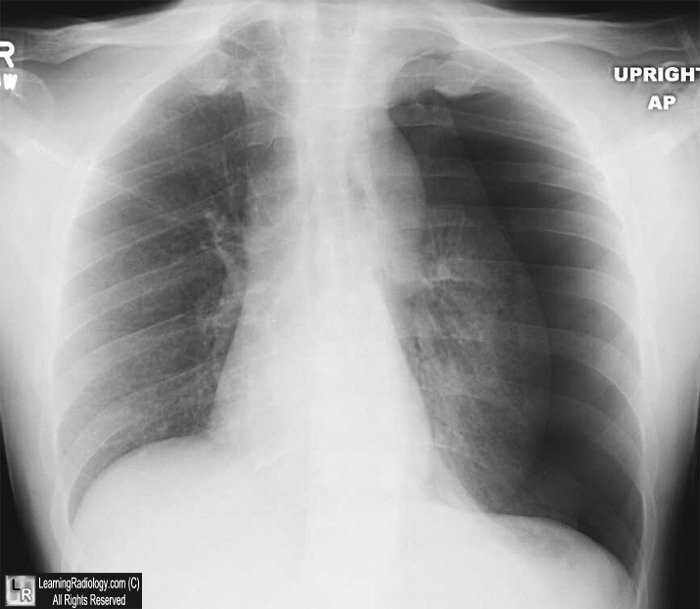

患者男性,23岁,被刺后出现刺痛,胸片如图1。最可能的诊断是什么?

图1

诊断:张力性气胸